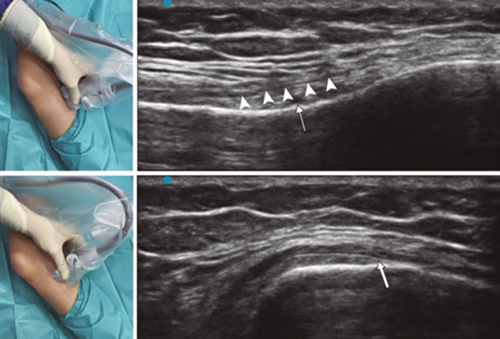

Para lograr una correcta ubicación de las referencias anatómicas por ultrasonido debemos colocar al paciente en posición supina con la rodilla flexionada y una almohada debajo de la fosa poplítea (14,16,19). Después de realizar asepsia/antisepsia de la rodilla, colocación de campos quirúrgicos y de la funda estéril del transductor lineal de alta frecuencia, procedemos a ubicar el NGSM (Figura 3). Colocando la sonda en un plano coronal sobre la cara interna de la rodilla, la deslizamos en sentido craneal hasta visualizar la unión de la metáfisis con la diáfisis femoral y la arteria/nervio geniculado superomedial (ANGSM), usualmente están localizados cerca al periostio del fémur (en caso de no encontrar esta estructura neurovascular, se toma como referencia la unión de la metáfisis y la diáfisis femoral). Después se marca en la piel el punto medio del transductor que corresponde a la ANGSM y se gira el transductor para ubicarlo en el plano transversal o axial para visualizar la ANGSM en eje corto (si no es posible la visualización de esta estructura, confirmar que estamos a un 50 % de la profundidad del fémur). En este corte transversal se avanza la aguja de RFT en plano desde anterior a posterior hacia la ANGSM o hasta una profundidad del 50 % del espesor del fémur. Finalmente se vuelve a girar el transductor 90°, dejándolo en un plano coronal para comprobar que la punta de la aguja está cerca de la ANGSM o de la unión de la metáfisis y la diáfisis femoral (14,16,19).

Fig. 3. Sonoanatomía y técnica para realizar el bloqueo del nervio geniculado superomedial (NGSM). El transductor se ubica en el eje largo distal del fémur y una vez que se tenga la posición del NGSM (asteriscos), se gira la sonda 90 grados para obtener una visión en eje corto del fémur (no olvidar mantener la misma profundidad a la que encontramos el NGSM en el eje largo). VM: vasto medial.

Para ubicar al NGIM (Figura 4) colocamos el transductor en un plano coronal sobre la cara interna de la rodilla, lo deslizamos en sentido caudal hasta identificar la unión de diáfisis con la metáfisis tibial y la arteria/nervio geniculado inferomedial (ANGIM), y repetimos los mismos pasos que usamos para el NGSM. En caso de no encontrar la ANGIM, la referencia que se tomará será la profundidad del 50 % del espesor de la tibia (14,16,19).

Fig. 4. Sonoanatomía y técnica para realizar el bloqueo del nervio geniculado inferomedial (NGIM). El transductor se ubica en el eje largo proximal de la tibia e identificamos el paquete vasculonervioso del NGIM (flecha) justo debajo ligamento colateral medial (puntas de flechas). Luego se gira la sonda 90 grados para obtener una visión en eje corto de la tibia (no olvidar mantener la misma profundidad a la que encontramos el NGIM en el eje largo).

Para ubicar el NGSL, el paciente debe estar en posición supina con el miembro inferior en rotación interna, consiguiendo una buena exposición de la cara lateral del muslo. Colocamos el transductor lineal en un plano coronal sobre la cara lateral de la rodilla, lo deslizamos en sentido craneal hasta visualizar la unión de la metáfisis con la diáfisis femoral y la arteria/nervio geniculado superolateral (ANGSL), y repetiremos los mismos pasos que usamos para el NGSM (14,16,19).

Después comprobamos que el umbral de estímulo sensitivo a 50 Hz que desencadene una parestesia o dolor sea menor de 0,6 V, y para evitar daño de nervios motores no debe existir fasciculaciones del miembro inferior con un estímulo motor a 2 Hz con 2,0 V. Si todo está correcto, administramos 2 ml de lidocaína al 2 % o mepivacaína al 2 % en cada nervio y procedemos a realizar la RFT a 80 °C durante 90 segundos (9,14).